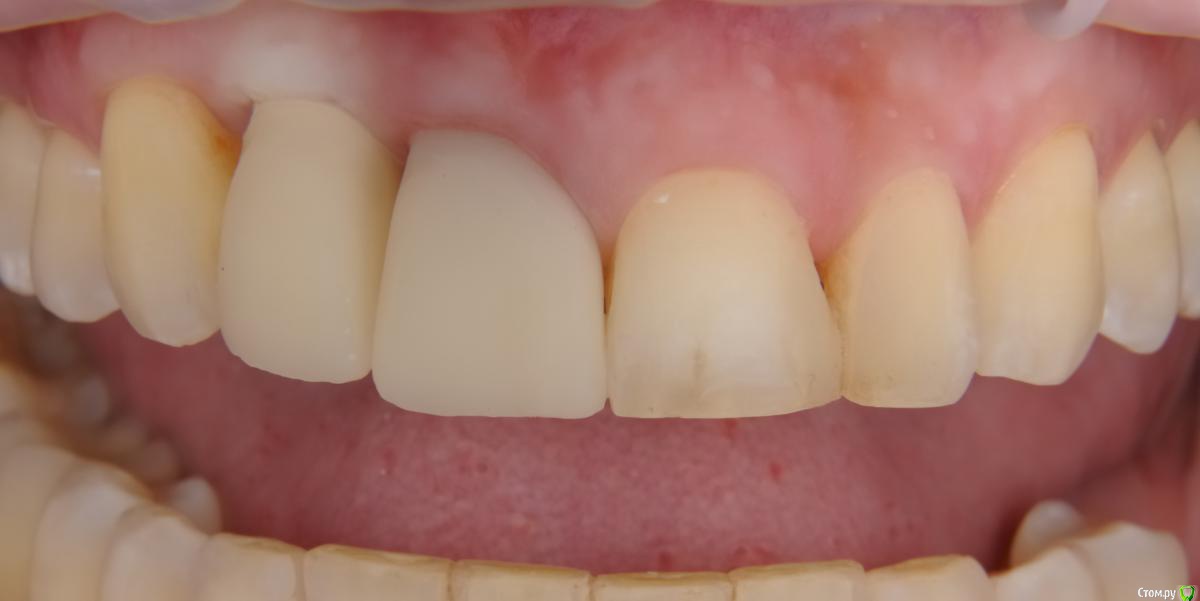

x4ex Опубликовано 30 августа, 2019 Поделиться Опубликовано 30 августа, 2019 Коллеги, как оцениваете прогноз пластики десны с целью коронального смещения зенитов 11 и 12 и создания сосочка между 11 и 12? 12 - имплантат. Ссылка на комментарий

x4ex Опубликовано 1 сентября, 2019 Автор Поделиться Опубликовано 1 сентября, 2019 11 МК коронка?пресс на примерке Ссылка на комментарий

Евгений Ходыкин Опубликовано 1 сентября, 2019 Поделиться Опубликовано 1 сентября, 2019 Сперва «тянуть» 1.1 с целью смещения зенита и возможной коррекции пики дистально. 1 Ссылка на комментарий

Dman Опубликовано 3 сентября, 2019 Поделиться Опубликовано 3 сентября, 2019 рассмотрите как вариант хир удлиннение 21, 22 + пластика 11, 12. В любом случае результат будет чуть лучше. 3 Ссылка на комментарий

Dman Опубликовано 4 сентября, 2019 Поделиться Опубликовано 4 сентября, 2019 так по снимку 12 - свой зуб! 358.jpg это резорбция у шейки или недозаглубили? по всем снимкам 12- имплант, вы точно врач? опишите пожалуйста, каким именно? ну видно же, что на примерке ишемия, значит абатмент выталкивает мягкие ткани вестибулярно и коронально. Если делать пластику то трансплантат будет находиться и расти в том же направлении. Значит нужно сделать более вогнутый абатмент с переходом в коронку намного ниже, там, куда мы хотим сместить зенит. а для чего глушить? чтобы получить больше мягких тканей, потом сместить их вестибулярно, и получить необходимую высоту. Также будет возможность провести на раскрытии еще пластику и добавить ещею 1 Ссылка на комментарий

Дмитрий М Опубликовано 8 сентября, 2019 Поделиться Опубликовано 8 сентября, 2019 ну видно же, что на примерке ишемия, значит абатмент выталкивает мягкие ткани вестибулярно и коронально. Если делать пластику то трансплантат будет находиться и расти в том же направлении. Значит нужно сделать более вогнутый абатмент с переходом в коронку намного ниже, там, куда мы хотим сместить зенит.понял, спасибо. так и у 11 тоже нужно сделать более вогнутую коронку и зенит опустить!? Ссылка на комментарий